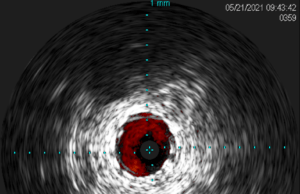

Tag: IVUS

Proceedings from an expert consensus roundtable that discussed the benefits of intravascular ultrasound (IVUS) in lower extremity revascularization procedures were released today in the...

The benefits of utilizing intravascular ultrasound (IVUS) in peripheral vascular interventions has been widely demonstrated in the literature. In...

Intravascular ultrasound (IVUS) is now used in a wide variety of peripheral vascular interventions after having first been utilized...